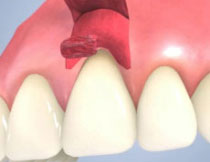

| 歯茎にプラーク(歯垢着が)と歯石の沈認められます。歯肉が腫れ、出血がありました。 | 歯科衛生士の治療と、ブラッシング技術の向上により、歯茎が引き締まり健康的な状態になりました。 | |